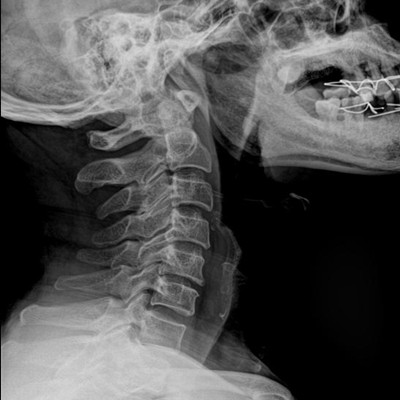

高品質影像鏈 讓您看的更清晰 PLX8500C/D

●大尺寸非晶硅平板探測器。

●探測器可以大范圍轉動,大尺寸有效探測面積,可滿足人體多部位攝影需求。